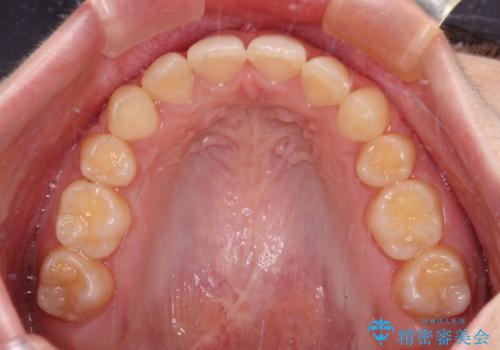

下顎の左右側切歯2本が欠損しており、上顎歯列がデコボコとなっている状態でした。

下顎歯列に対して上顎歯列が相対的に大きくなっているため、デコボコとなっているだけでなく、下顎前歯が見えなくなるくらいのディープバイトにもなっていました。

上顎左右第一小臼歯2本を抜歯し、ワイヤー装置にて矯正治療を行うこととしました。

通常の抜歯矯正と抜くべき歯の位置が異なるため、咬みにくさが残ってしまうのではないかと懸念されましたが、咬み合わせに違和感なく、スムーズに治療を終えることができました。